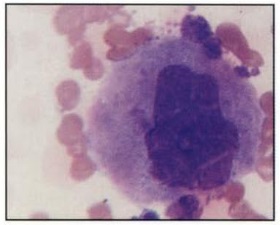

Pronormoblasto

Aumento: 1000x

Tinción: Wright-Giemsa

(Carr, 2010)

SERIE ROJA

Tamaño: 12-20 µm

Tamaño: 12-20 µm

Núcleo: redondo a ovalado, acidófilo

Nucléolos: 1-2

Cromatina: contiene grumos fina

Citoplasma: teñido se observa basófilo

Organelos: complejo de Golgi, puede ser visible cerca del núcleo

Relación N/C: 8:1

Se encuentra en Médula ósea en un intervalo de 1%

Tiempo de tránsito en médula ósea de 12 horas

Ausente en sangre periférica

También llamado Proeritroblasto o Rubriblasto

Función: precursor eritroide, sufre mitosis para dar origen al normoblasto basófilo.